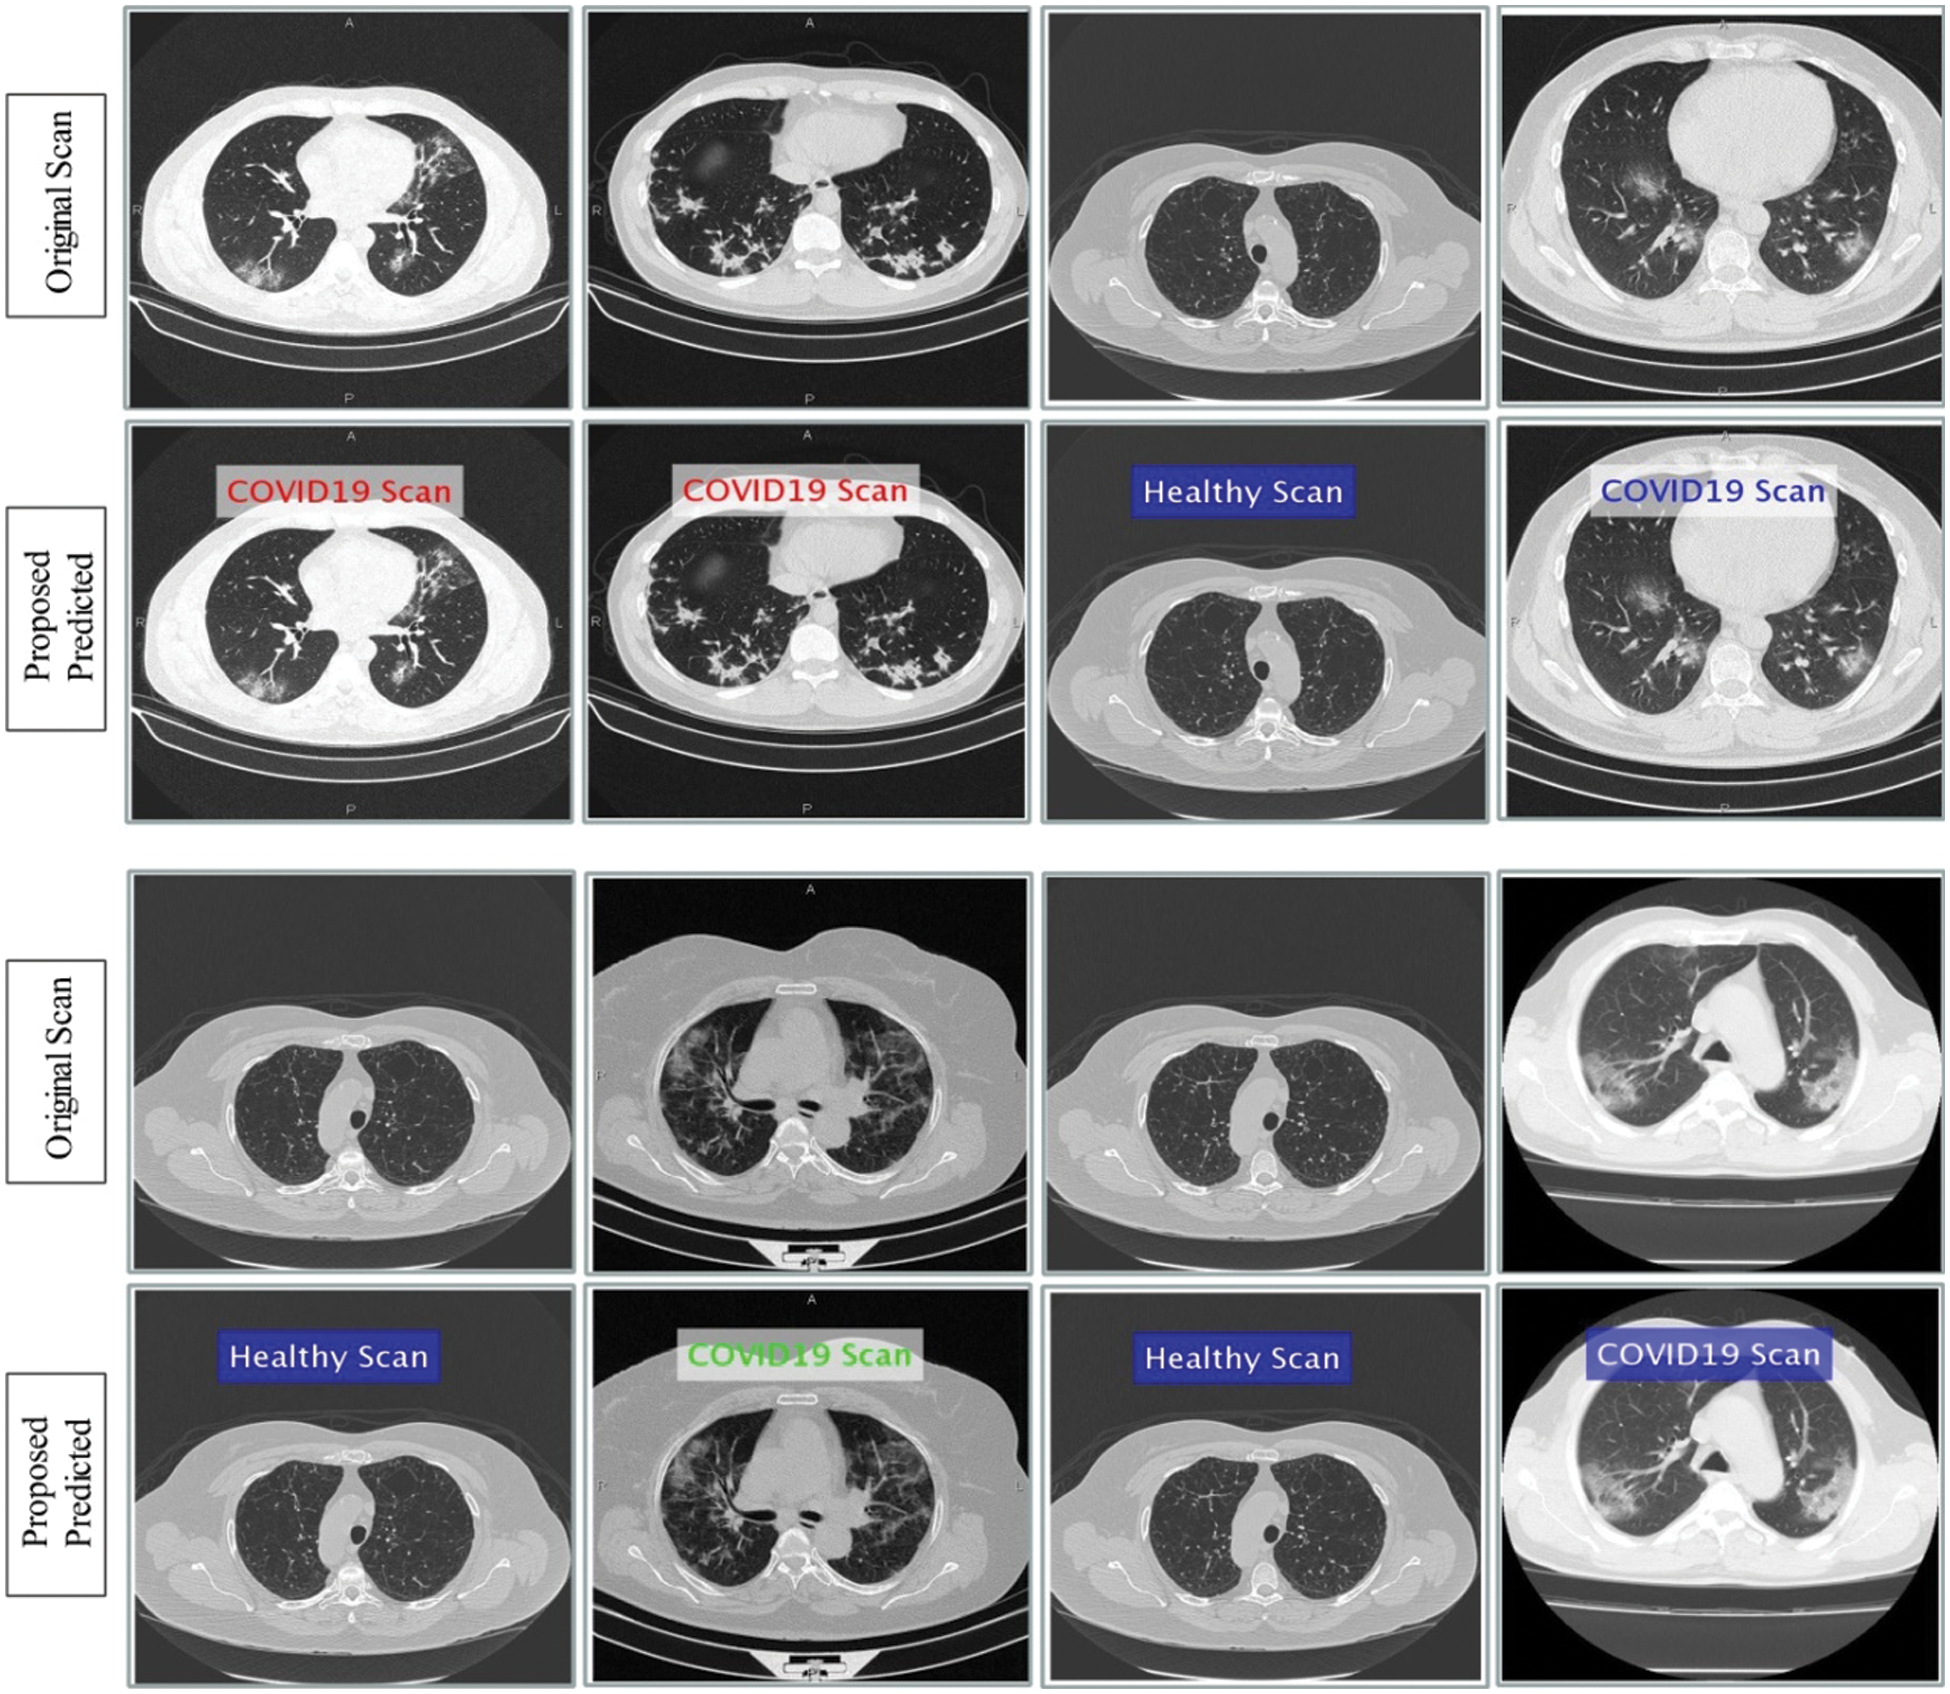

This section presented the detailed discussion of presented method in terms of calculated performance metrics and visual plots. As described in the introduction section that we are dealing with Chest CT scans for prediction of COVID19 positive and healthy images. These sample scans are showing in Fig. 1. The main problem is classifying these scans using computer vision. For this purpose, we proposed a, integrated model based on multiple features fusion and improved PSO based selection. Fig. 2 shows the main architecture diagram. In this figure, it is showing that multiple features are extracted and fused in one matrix using Maximum Covariance approach. The fusion process improves the image information for correct prediction; however, it is chance to add many irrelevant features as visual representation is showing in Fig. 5. The quantitative results are presented in Tab. 1, which shows the maximum accuracy is 88.6%. Figs. 8, 9 and 10 also support the proposed accuracy. Later, improved PSO is applied on fused feature matric and selects the most informative features. Visually, these features are showing in Fig. 6. From this figure, it is shown that the number of features is minimized after applying improved PSO. Tab. 2 shows the quantitative results of results of proposed selection method with the accuracy of 93.1%. Also, Figs. 11, 12 and 13 support this accuracy. This accuracy is improved as compared to fusion step. For comparison, we compute the accuracy of each feature type separately and then compare with fusion and selection process. Fig. 14 shows the feature based comparison. In this figure, it is observed that the accuracy of original extracted features like DWT, DCT, DRLBP, and Shanon entropy along Kurtosis (SEaK) is 79.8%, 83.2%, 80.6%, and 82.1%, respectively. However, after the fusion process, 6% accuracy is increases. Further, the selection process, also improves the features which effect show in the accuracy. This last step, selects only informative features that improves the accuracy of correct prediction. A few predicted results by presented system are shows in Fig. 15. These results are obtained in the testing process. Overall, proposed system give significant performance for prediction of COVID19 scans.

Figure 15: Prediction of COVId19 positive and healthy Chest CT Scans using proposed method